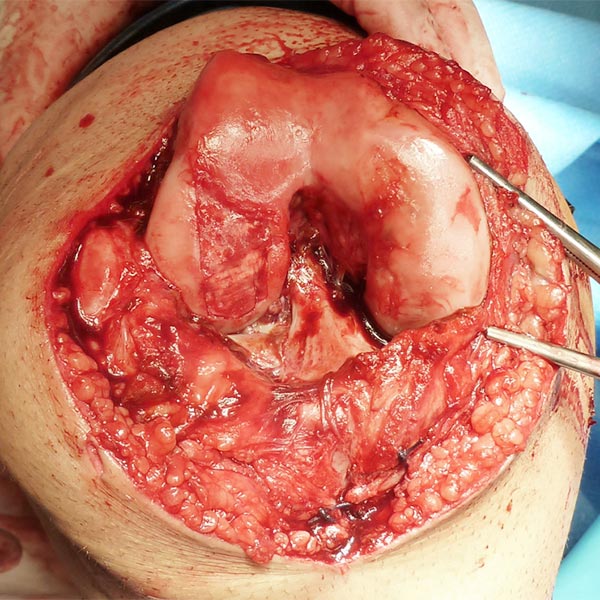

Intraoperative image after opening of the knee joint. The synovium is severely hyperplastic due to the recurrent inflammatory processes of the thrombophlebitis and interspersed with venous malformation. Owing to contained blood in the venous malformation, it appears darkly discolored. Part of the cartilage defect is also visible.